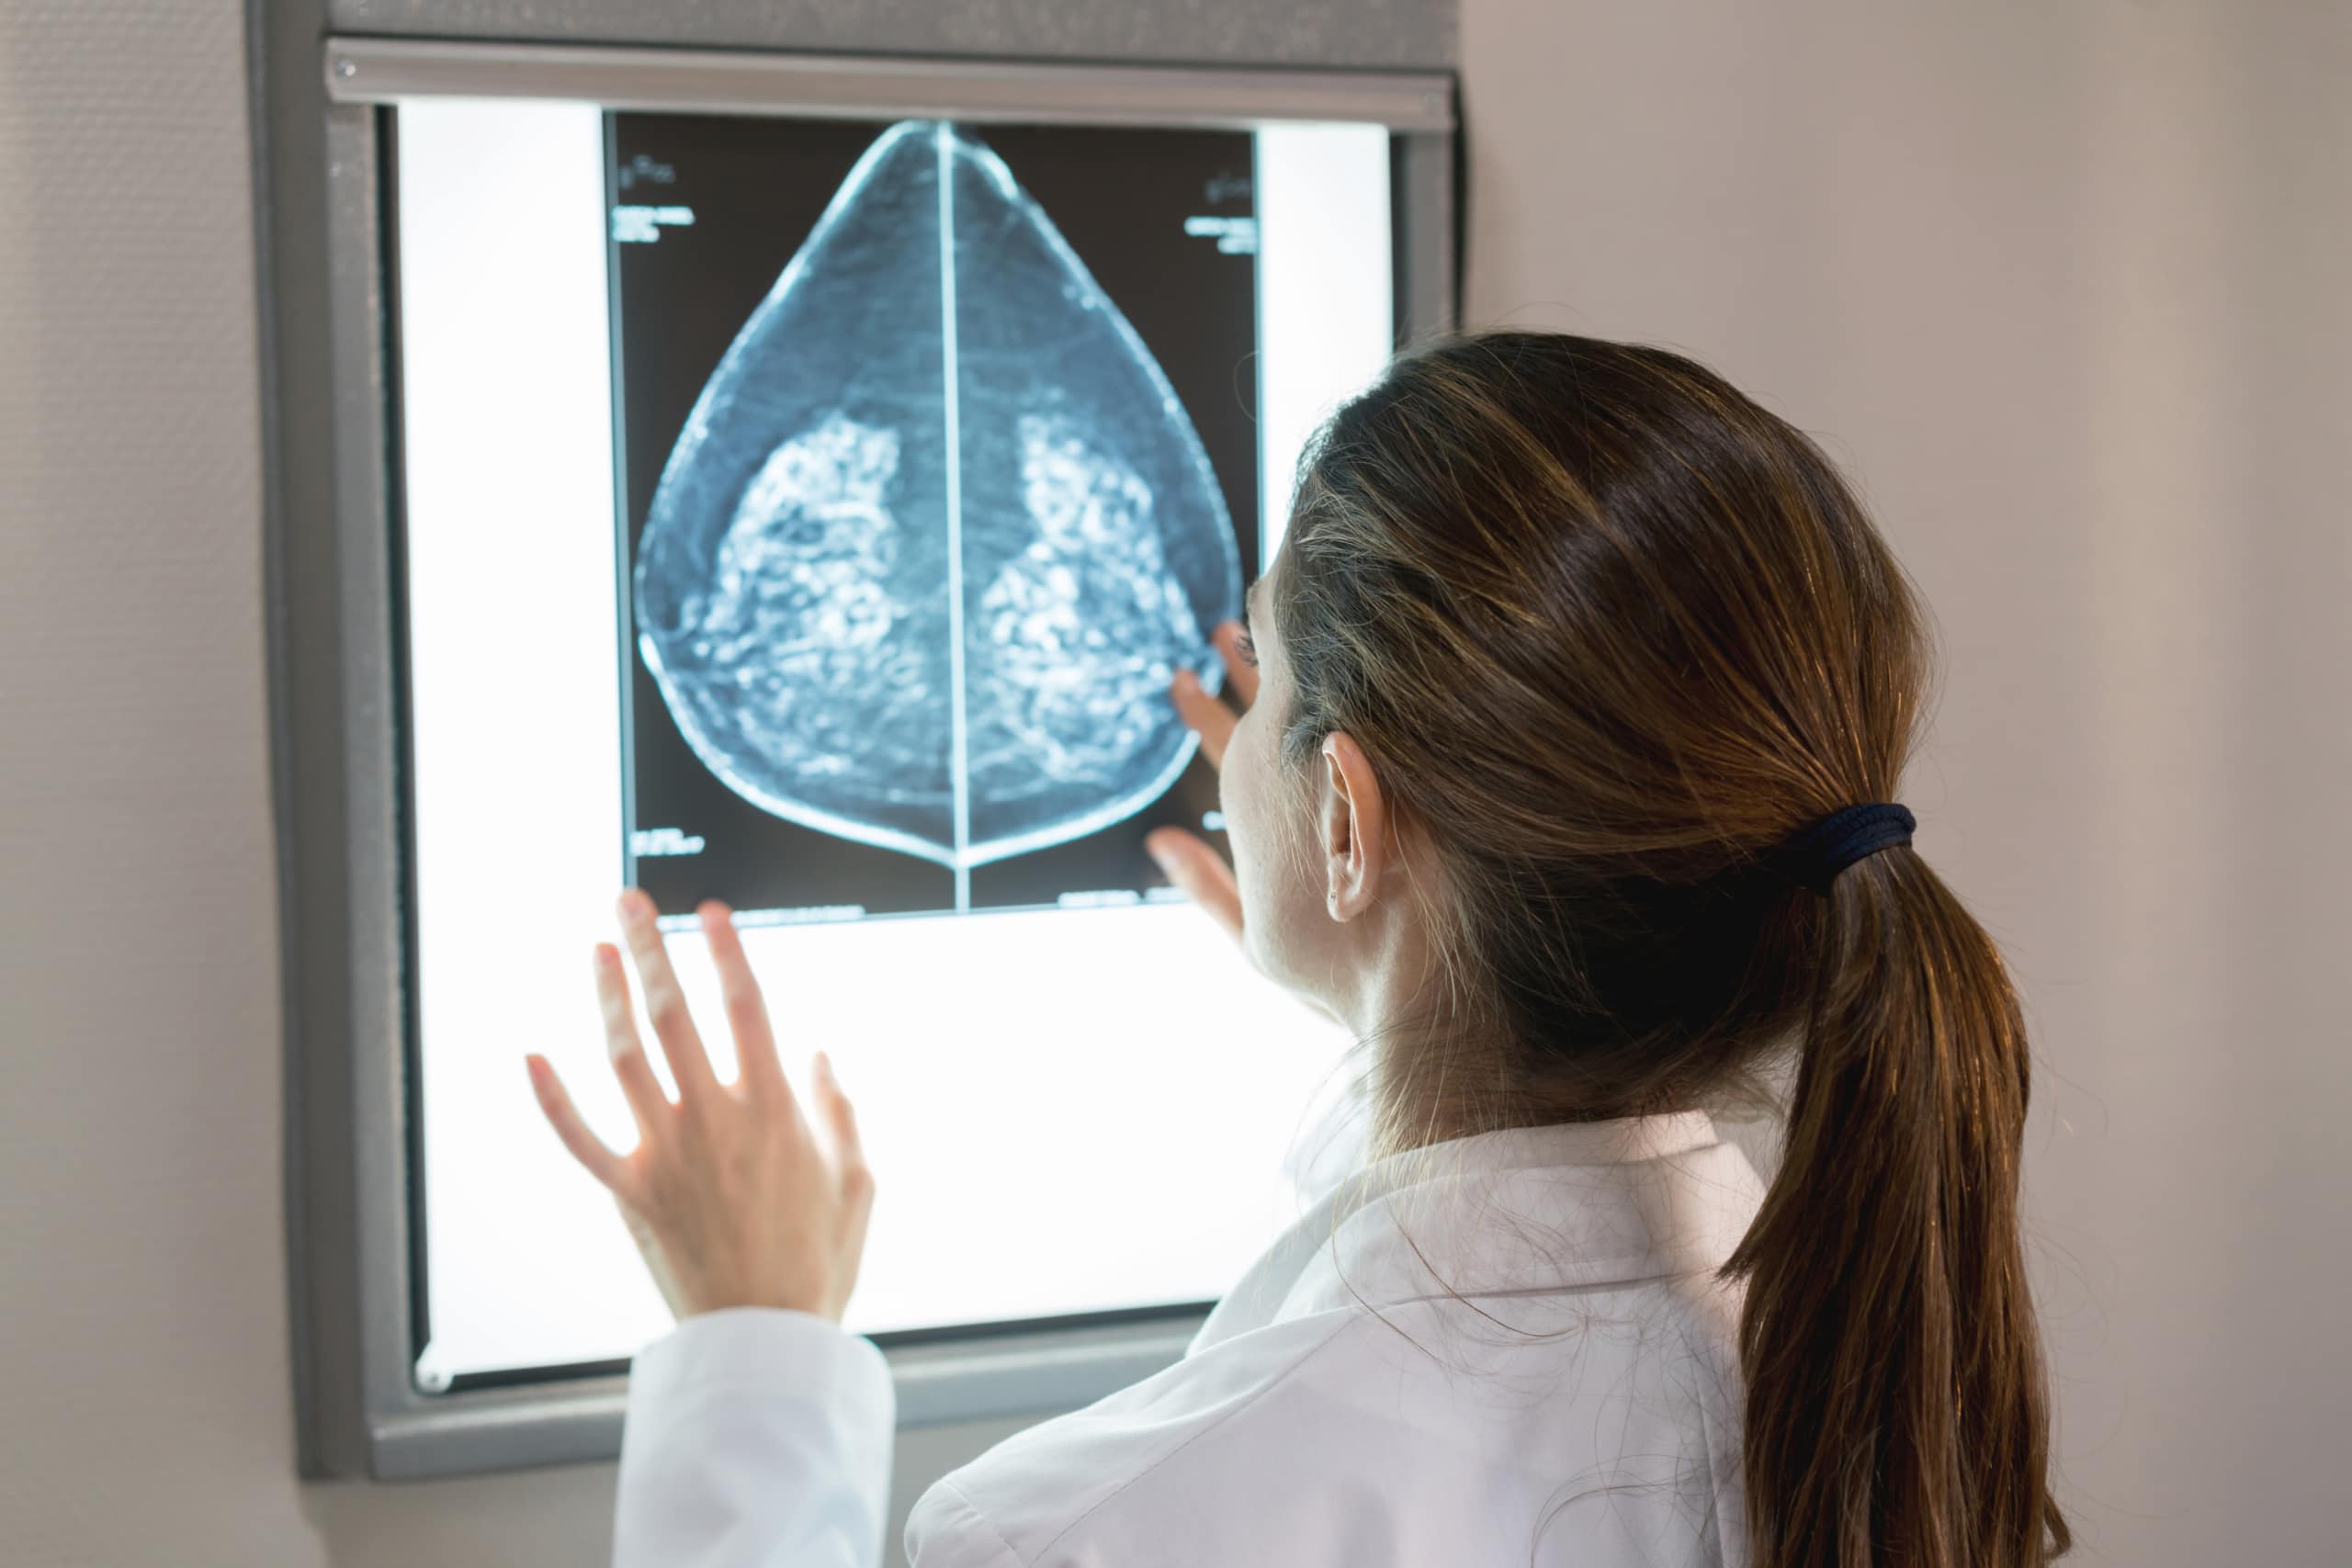

Treatment for breast cancer in men involves most of the same options as for women – surgery, chemotherapy, radiotherapy and hormone therapy. However, there are variations as to how these treatments are carried out.

The most common type of surgery for men with breast cancer is a mastectomy, where the whole breast is removed. Breast conserving surgery, where only the part of the breast with the cancer is removed, is generally not suitable due to the lack of breast tissue in men.